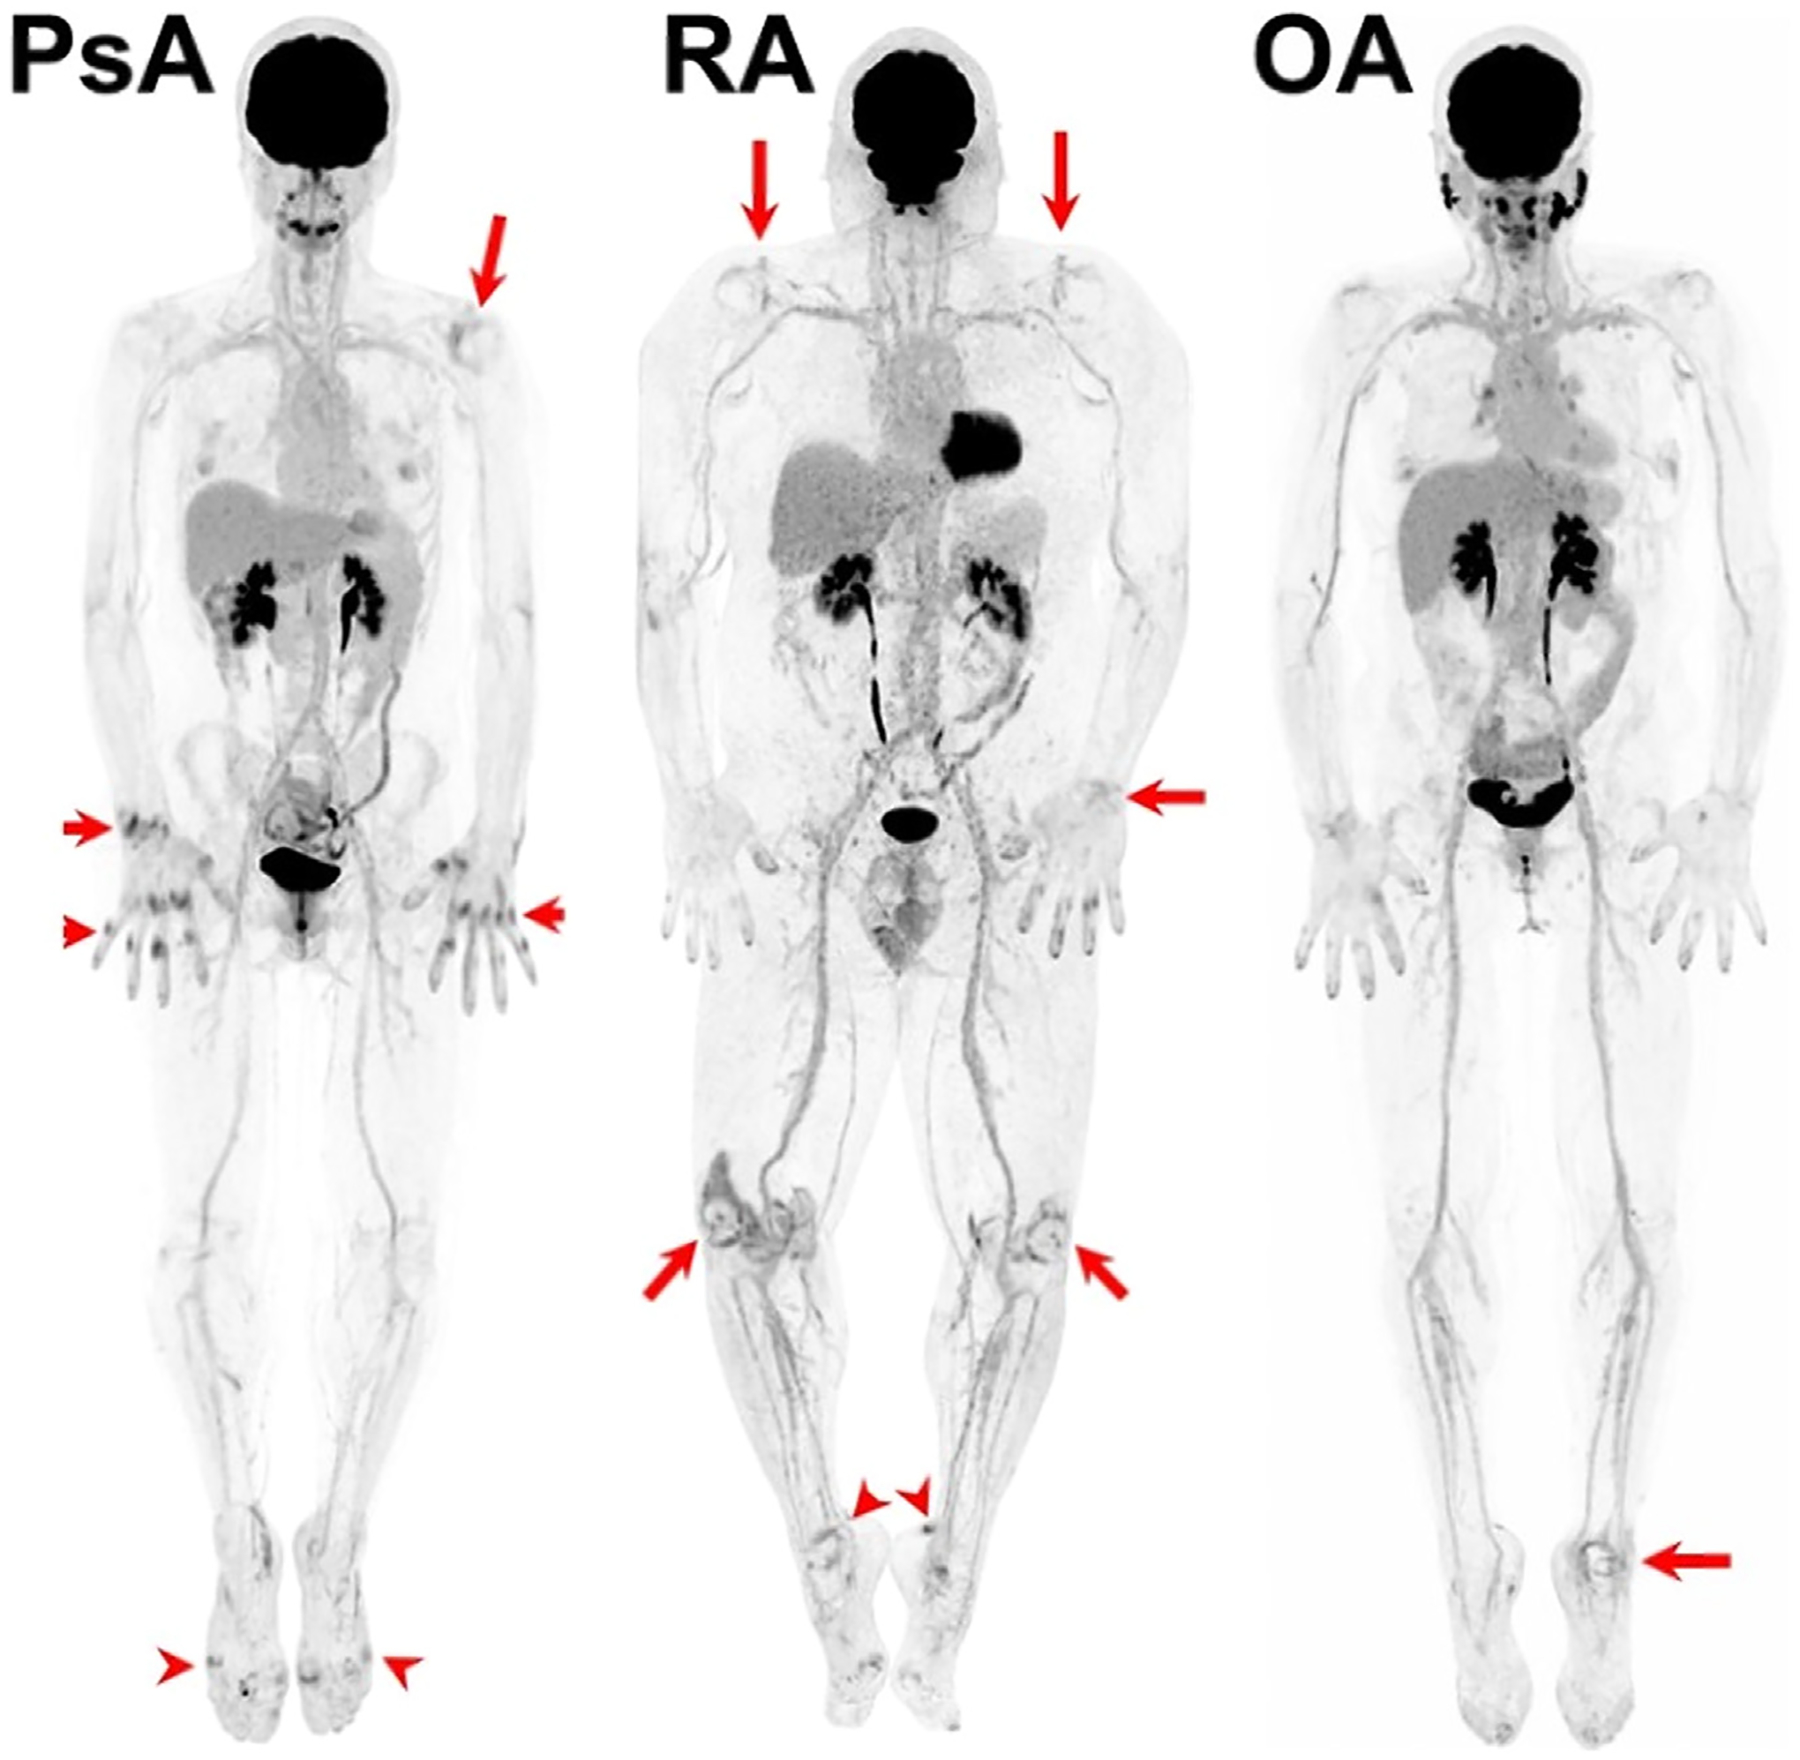

Inflammatory disorders historically have been difficult to monitor with conventional PET imaging due to limitations including radiation exposure, lack of validated imaging biomarkers, low spatial resolution, and long acquisition durations. However, the recent development of long-axial field-of-view (LAFOV) PET/CT scanners may allow utilization of novel noninvasive biomarkers to diagnose, predict outcomes, and monitor therapeutic response of inflammatory conditions. LAFOV PET scanners can image most of the human body (if not the entire body) simultaneously in one bed position, with improved signal collection efficiency compared to conventional PET scanners. This allows for imaging with shorter acquisition durations, decreased injected radiotracer dose, prolonged uptake times, or a combination of any of these. In addition, LAFOV PET scanners enable whole-body dynamic imaging. Altogether, these intrinsically superior capabilities in assessing both local and systemic diseases, have allowed these scanners to make increasingly significant contributions to the assessment of inflammatory conditions. This review aims to further explore the role and benefits of LAFOV scanners for imaging various inflammatory conditions while addressing future developments and challenges faced by this technology.